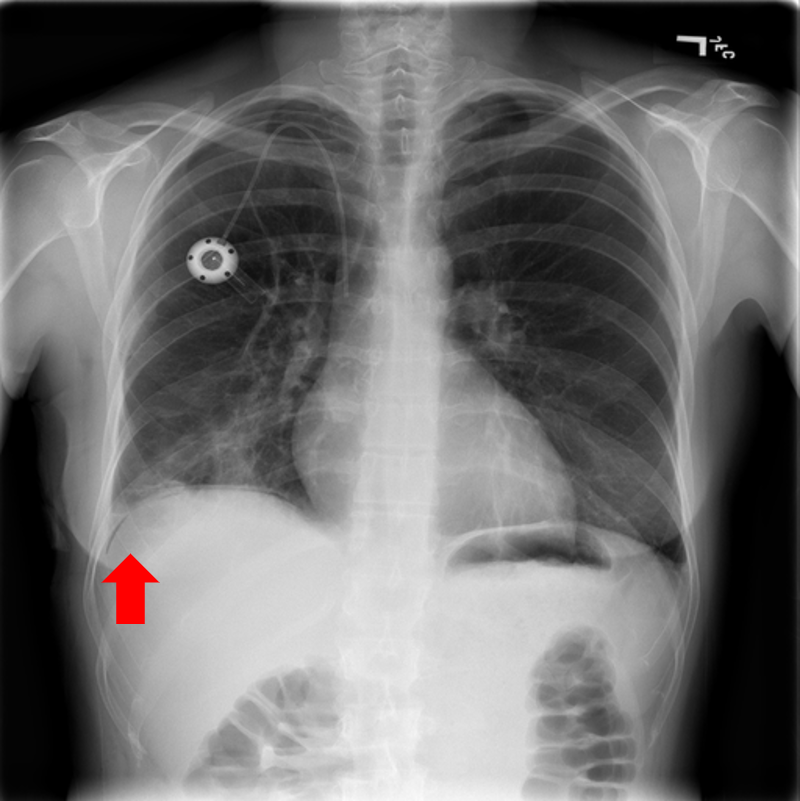

Figure 9: Typical CXRs with pneumonia-like lung opacity from among the top 1,000 CXRs most likely to have an abnormality according to the logarithm posterior probability out of the 13,863 abnormal CXRs. The lesion is indicated with a red arrow if applicable.

Figure 9 shows CXRs suggested to have pneumonia-like lung opacity with the logarithm posterior probability. These CXRs are the top 1,000 CXRs most likely to have an abnormality out of the 13,863 abnormal CXRs.